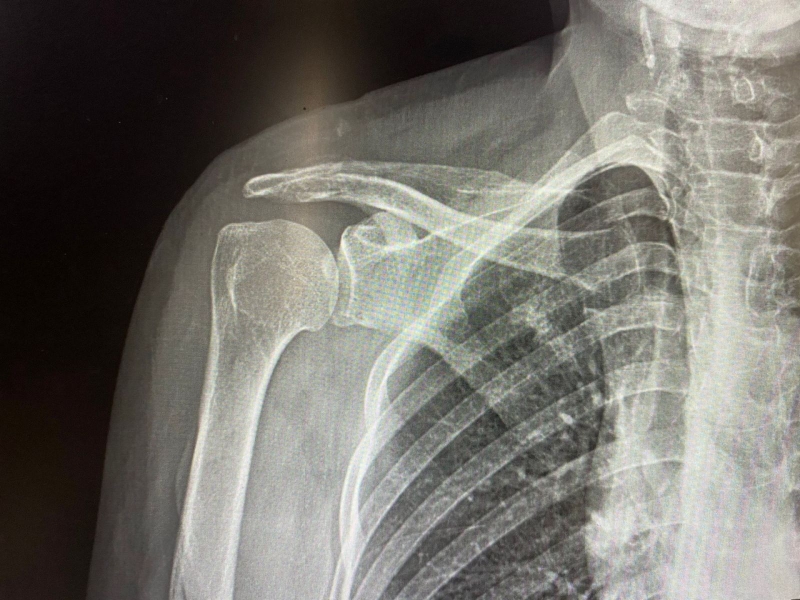

Hầu hết khi xương đòn bị gãy thường sẽ được cố định và the o dõi ở nhà bằng cách sử dụng một chiếc đai có hình tam giác để hỗ trợ cánh tay và giữ các xương lại với nhau. Các loại đai cố định thường được đeo ngay sau khi chụp X-quang sau khi xác nhận chẩn đoán xương đòn bị gãy. Người bệnh sẽ được bác sĩ cho uống thuốc giảm đau để làm giảm cơn đau do gãy xương đòn và tình trạng đau sẽ giảm dần theo thời gian.

Gãy xương đòn bao lâu đi xe máy được 1 Phương pháp điều trị gãy xương đòn phụ thuộc vào mức độ nghiêm trọng của vết gãy